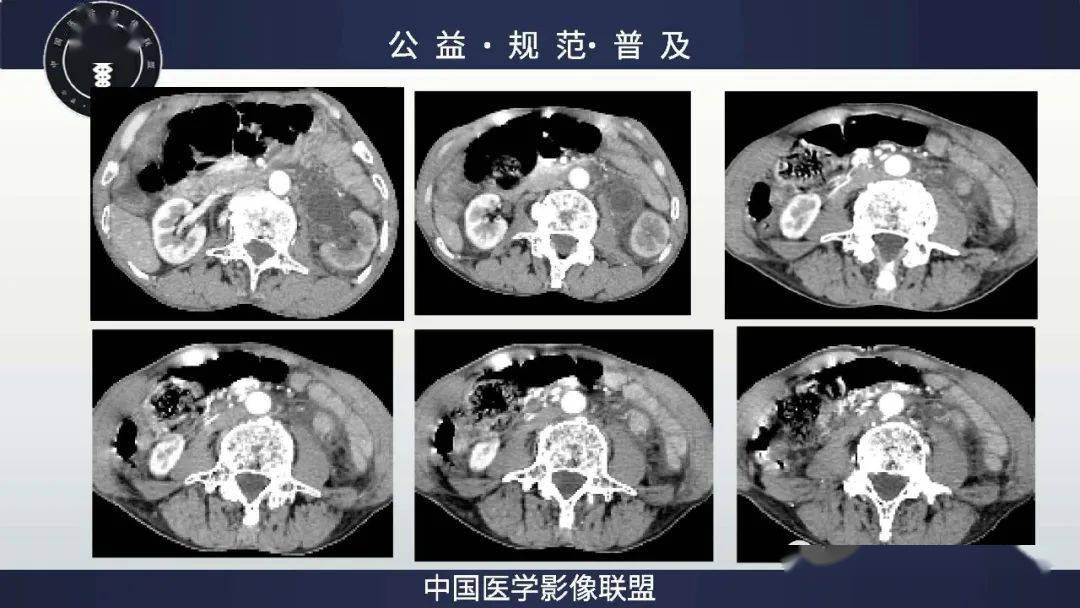

浸润性肾盂输尿管尿路上皮癌1例 - 好大夫在线

图片尺寸1200x1600